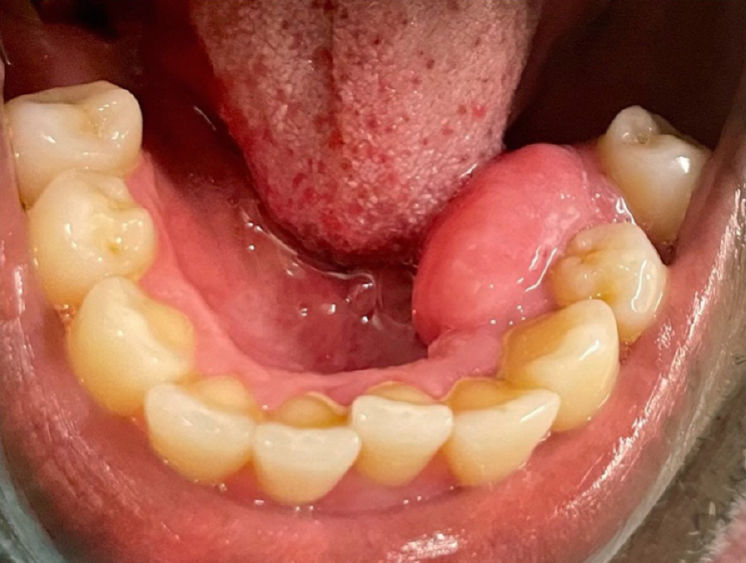

При внешнем осмотре не выявлялось асимметрии или лимфаденопатии. При осмотре полости рта обнаружено безболезненное, одностороннее, чётко очерченное, одиночное сидячее образование, локализованное на язычной прикреплённой десне в области левых нижних премоляров (показано на фото). Изъязвления поверхности не наблюдалось. Другие стоматологические находки включали заболевания пародонта, обусловленные отложением зубного камня, кариес и отсутствие нескольких зубов.

Фото 1. Клиническая фотография десневого образования на язычной поверхности левой половины нижней челюсти в области премоляров, демонстрирующая смещение зуба 35. Образование распространяется от медиальной поверхности зуба 35 до дистальной поверхности зуба 33